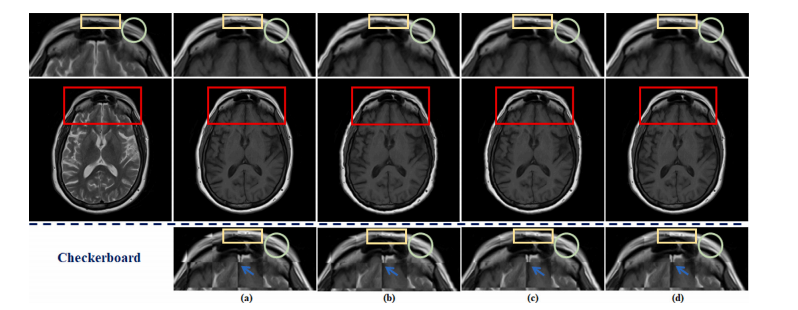

Fig. 10. The visualization of the effects of spatial alignment on the fastMRI dataset. (a) shows the original fully-sampled T1 image. (b) represents the results of aligning anunder-sampled T2 image with a fully-sampled T1 image by traditional method. © depicts the results of integrating traditional spatial alignment with reconstruction for jointoptimization. (d) displays the result of DUN-SA. Details are shown in the first row: zoomed-in view of aligned T1 images and third row: zoomed-in views of checkerboardvisualizations

图10. 空间对齐对 fastMRI 数据集的影响可视化。(a) 显示原始完全采样的 T1 图像。(b) 表示通过传统方法将欠采样的 T2 图像与完全采样的 T1 图像对齐的结果。© 描述了将传统空间对齐与重建整合进行联合优化的结果。(d) 显示 DUN-SA 的结果。具体细节见第一行:对齐的 T1 图像的放大视图,第三行:棋盘可视化的放大视图。